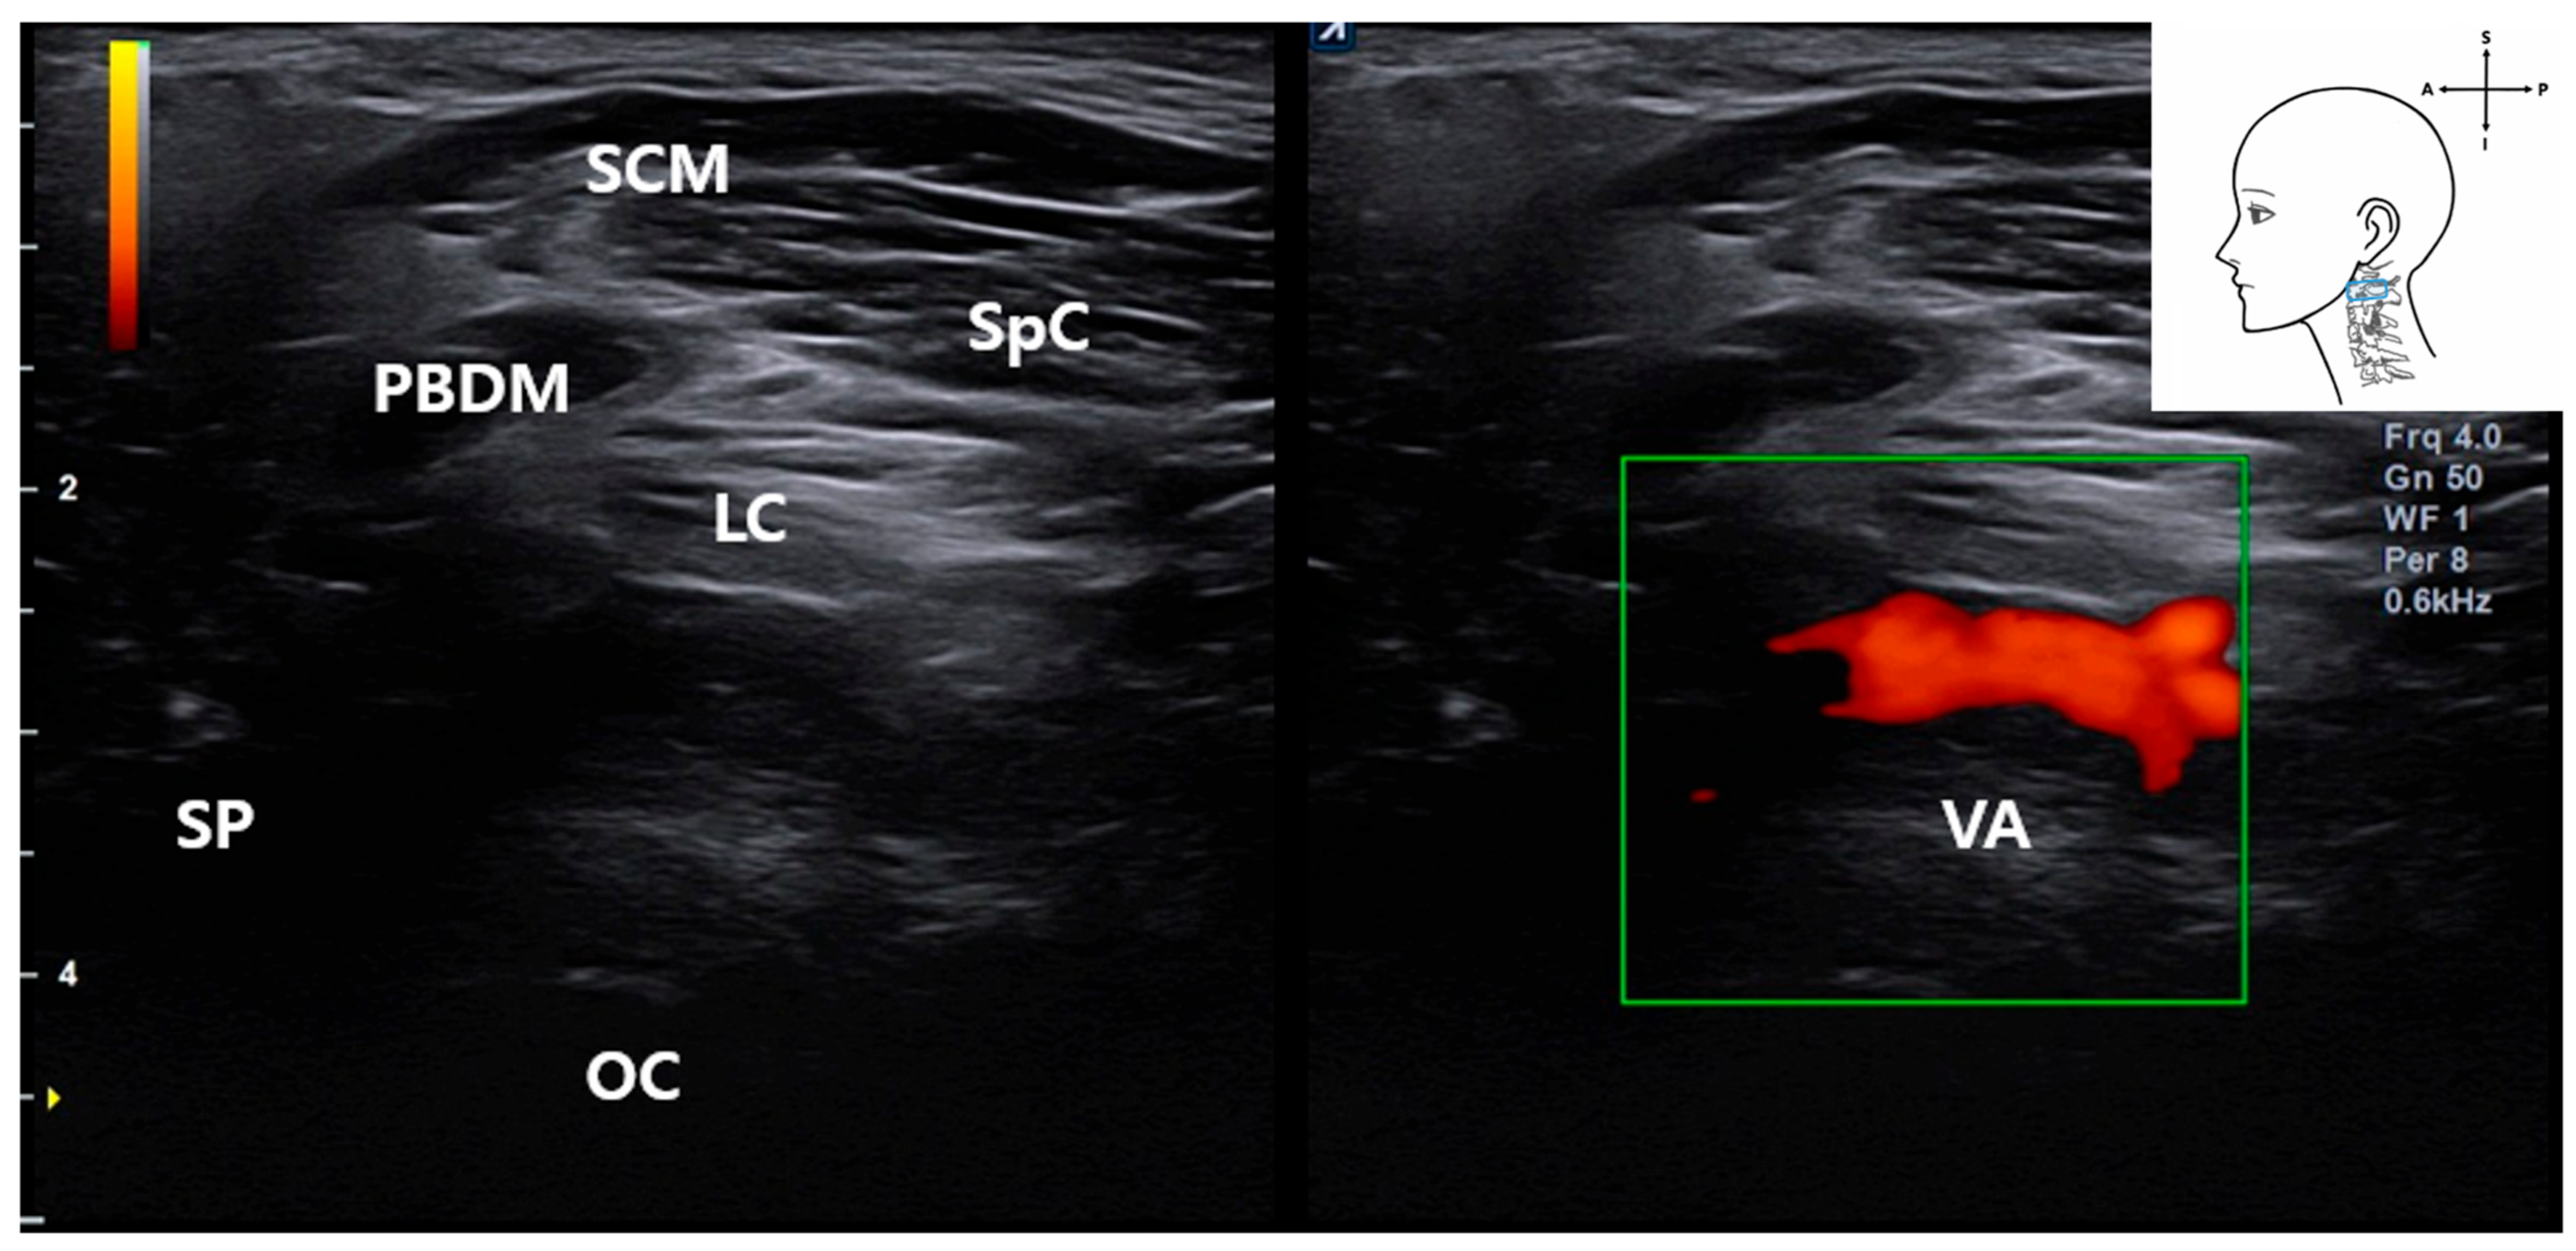

3.4. Identification of the Vertebral Artery (VA)